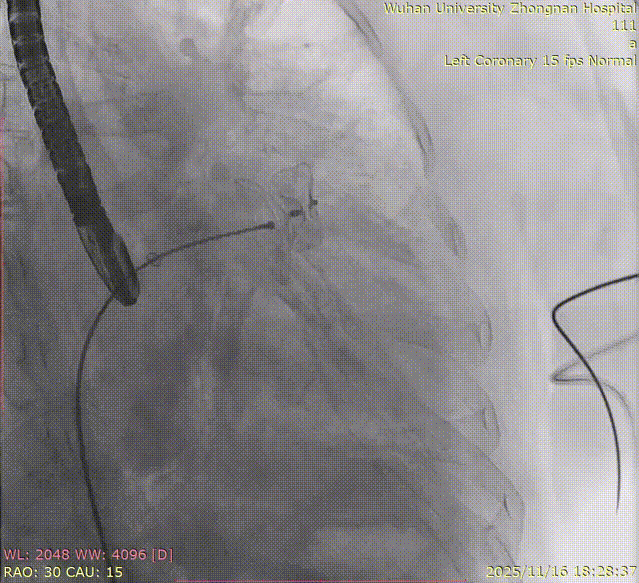

The entire procedure was guided by both Transesophageal Echocardiography (TEE) and Digital Subtraction Angiography (DSA).

Left Atrial Appendage Closure (LAAC):The delivery system was successfully advanced into the left atrium. Precise measurements of the LAA orifice and depth were taken under multi-angle TEE and DSA guidance. Given the LAA's large orifice (nearly 34mm), conical cauliflower shape, and shallow usable depth, a LACBES2434 occluder was selected. Using the "extreme coin technique," the closure was successfully achieved.

DSA

5.Right coronary angiography confirming no impact on the RCA after clipping.

8.Right coronary angiography confirming no impact on the RCA before releasing the second implant.